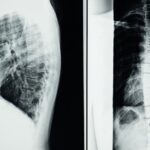

La décompression spinale est une technique thérapeutique qui utilise des appareils spécialement conçus pour créer une pression négative au sein des disques intervertébraux. En réduisant cette pression, la méthode favorise la réhydratation des disques, contribuant à la réparation des tissus endommagés et à la réduction de la douleur. Cette approche est particulièrement efficace pour traiter les affections comme les hernies discales et la sténose spinale.

Les résultats des études cliniques sur la décompression neurovertébrale ont révélé des taux d’amélioration significatifs chez les patients, pouvant atteindre jusqu’à 91%. Ces statistiques témoignent de l’efficacité de la technique dans la réduction des douleurs chroniques, des sensations de picotement et des engourdissements causés par des compressions nerveuses. En offrant une alternative non invasive, cette méthode change la donne pour de nombreux patients qui souhaitaient éviter la chirurgie.

La décompression neurovertébrale est l’une des technologies phares utilisées par le Dr. Desforges et son équipe. Ce traitement non invasif induit une pression négative intra-discale, favorisant la réhydratation des disques et permettant ainsi une rétraction plus efficace des hernies discales. Les résultats sont prometteurs, avec des taux d’amélioration atteignant parfois 91 %. Cette approche offre une alternative à des procédures chirurgicales, souvent complexes et risquées, permettant aux patients de retrouver une qualité de vie satisfaisante.

La décompression neurovertébrale, en particulier, a su se démarquer par son efficacité prouvée. Elle offre des taux d’amélioration significatifs, atteignant parfois jusqu’à 91% selon certaines études. Cela témoigne d’une méthode dont les avantages dépassent les approches traditionnelles, visant à offrir aux patients un soulagement durable. En réduisant la pression intra-discale, cette technique favorise également la rétraction herniaire, jouant un rôle clé dans le traitement des hernies discales.